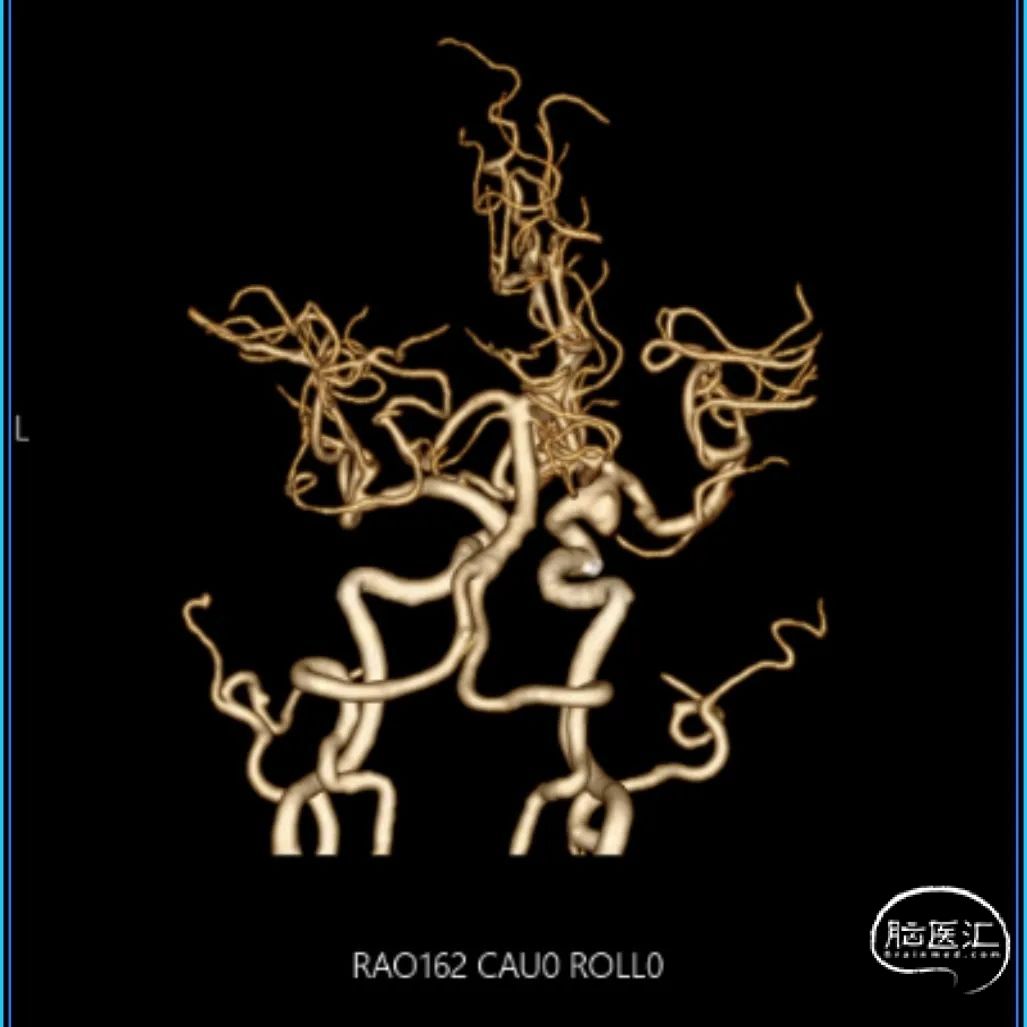

CTA:右侧颈内动脉C7段动脉瘤。

老年女性患者,检查发现右侧颈内动脉C7段大动脉瘤,动脉瘤直径大于10mm,形态不规则,宽颈,手术指征明确,既往高血压、肿瘤病史,首选微创介入手术,术中造影证实动脉瘤直径大于10mm,绝对宽颈,形态不规则,局部仔瘤改变,右侧脉络膜前动脉从瘤体发出;微创介入血流导向装置是较优选择。

DSA造影:

工作角度:

大动脉瘤的微创介入栓塞治疗存在需要支架辅助,瘤颈处理困难、复发率高、费用高等难点;血流导向密网支架置入是较优选择,操作相对简单,不用填塞弹簧圈,完整覆盖瘤颈,远期明显降低再复发概率。本病例为右侧颈内动脉C7段累及脉络膜前动脉的大动脉瘤,该部位解剖结构复杂,周围血管分支多,在操作过程中要避免损伤正常血管,否则会引发严重脑缺血事件;其次,动脉瘤与脉络膜前动脉关系密切,既要处理好动脉瘤,又要保证脉络膜前动脉的血供不受影响,这对手术操作精度要求较高;再者,瘤颈的处理较为棘手,瘤颈较宽,传统弹簧圈栓塞难以达到理想效果,且容易复发。血流导向密网支架置入可解决这些问题,术前需借助3D-DSA,全面评估动脉瘤大小、形态、瘤颈宽度、与周围血管关系,制定精准手术方案。操作时,微导管的到位是关键一步,要在路径图引导下,小心、轻柔操作,避免刺激血管引发痉挛或动脉瘤破裂。释放支架过程中,要注意关注支架位置和贴壁情况。释放后要通过多角度造影,确认支架完全覆盖瘤颈,且支架内血流通畅,分支血管未受影响。同时,术后要密切观察患者神经功能变化,预防血栓形成、血管痉挛等并发症,及时给予抗血小板、解痉等药物治疗。